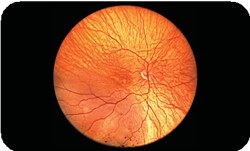

La solution d’imagerie pour la détection précoce des pathologies rétiniennes.

Le rétinographe Cellview WRI-1 Ultra-grand champ, permet le dépistage, le diagnostic et le suivi de l'ensemble des pathologies rétiniennes.

Le rétinographe Cellview WRI-1 permet de diagnostiquer les pathologies rétiniennes grâce à sa caméra rétinienne ultra-grand champ capable de capturer des images 2 à 3 fois plus grandes que la plupart des rétinographes existants.

Alors que les rétinographes traditionnels offrent un champ de 60°, la caméra rétinienne non mydriatique Cellview WRI-1 permet une capture de la rétine à 133° en une seule prise ou à 200° en deux prises avec l’assemblage automatique des deux images.

Ces fonctionnalités permettent de détecter, diagnostiquer et surveiller l’ensemble des pathologies rétiniennes, y compris les anomalies périphériques qui pourraient passer inaperçues avec des méthodes d'imagerie plus restreintes.

Simple d’utilisation et particulièrement intuitif, Cellview WRI-1 pénètre les couches les plus profondes de l'œil, même à travers les opacités et les petites pupilles, pour apporter une vue d’ensemble de la rétine et permettre la détection précoce des pathologies.